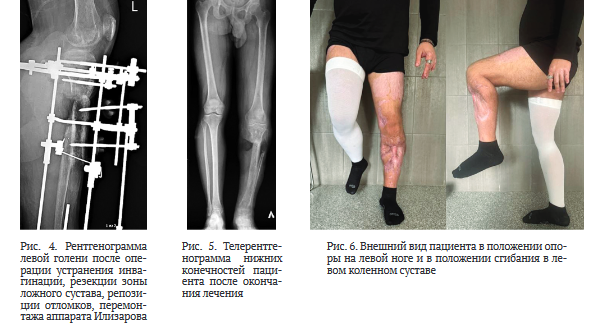

После стабилизации состояния и заживления ран на левой голени (рис. 1) через 72 дня после ранения провели операцию: внеочаговый чрескостный компрессионно-дистракционный остеосинтез (ВЧКДО) по Илизарову левой голени, остеотомия дистального отломка левой большеберцовой кости. Дефект большеберцовой кости — 15 см. На 79-е сутки после ранения начали перемещение фрагмента с целью формирования регенерата и замещения дефекта. На 164-е сутки после ранения (85 суток после остеотомии) для коррекции положения и направления перемещения фрагмента выполнили перемонтаж аппарата Илизарова на левой голени. Продолжили перемещение фрагмента дистального отломка большеберцовой кости (рис. 2).

На 261-е сутки после ранения (182-е сутки после остеотомии) отметили контакт фрагмента и проксимального отломка через зону инвагинации (рис. 3). В целях обеспечения контакта проксимального отломка и перемещаемого фрагмента дистального отломка на 262-е сутки после ранения (183-и сутки после остеотомии) выполнили резекции зоны инвагинации и костно-хрящевого комплекса на торце проксимального отломка и перемещаемого фрагмента, открытую репозицию отломков, перемонтаж аппарата Илизарова. Достигнут контакт торцевых частей проксимального отломка и перемещаемого фрагмента (рис. 4). В последующем проводили компрессию между проксимальным отломком и фрагментом, «воспитание регенерата» методом «аккордеона».

Сращение между проксимальным отломком и фрагментом, а также созревание регенерата отмечены на 493-и сутки, выполнили демонтаж аппарата Илизарова (рис. 5). Продолжили реабилитацию в течение 60 суток (рис. 6).

Общий срок лечения составил 553 суток, ИВФ — 43,7 сут./см, анатомический результат по шкале ASAMI — удовлетворительный, функциональный результат по шкале ASAMI — хороший.